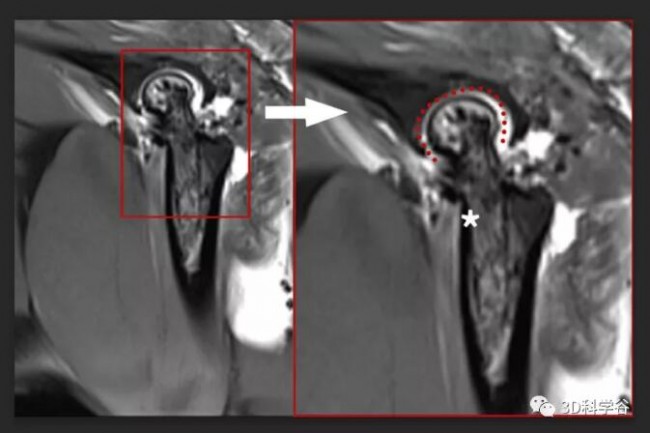

戴尅戎院士團隊在2003年獲得中國第一張個(ge) 性化人工關(guan) 節假體(ti) 注冊(ce) 證,此後,新的個(ge) 性化關(guan) 節植入物迭代研究開始向更高的耐用性和生物活性方向發展,其中麵臨(lin) 著血管化的難題——無血管長入導致細胞凋亡,是傳(chuan) 統組織工程生物型關(guan) 節假體(ti) 失效的常見原因之一。3D打印生物關(guan) 節實現血管化©上海第九人民醫院一項為(wei) 期 24 周的研究證明了3D 打印關(guan) 節的耐用性和功效,關(guan) 節具有光滑、幹淨的軟骨層的。

©上海第九人民醫院再生股骨頭軟骨與(yu) 再生軟骨下骨完美融合